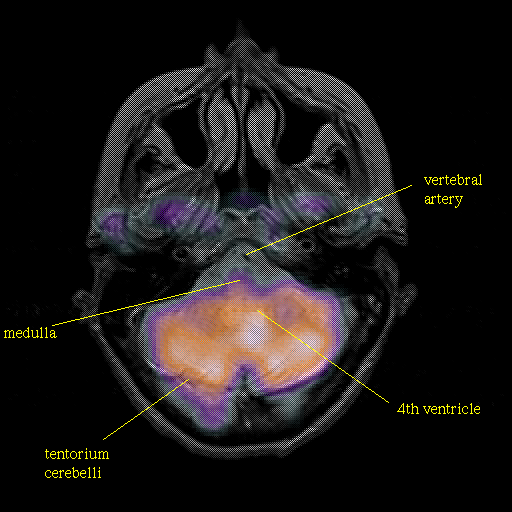

Pointers

Labeled